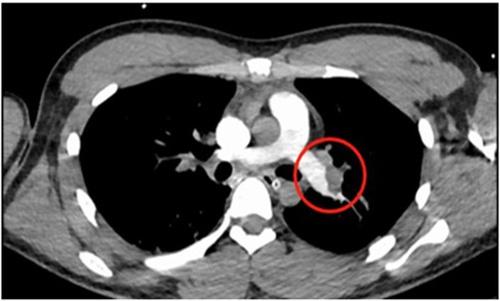

之后出現了第3次心臟的驟停,醫生按壓了三分鐘之后才恢復自主心率,被送入ICU進行對癥的治療,在血管造影等各項檢查之后通過檢查報告,能夠看到是肺栓塞。7月31日凌晨小韓大動脈搏活動消失,第4次心臟驟停,醫生在靜脈上推出腎上腺素,恢復自主心率。

這是小韓病情極為危重,專家認為是危重型的血栓性肺栓塞診斷上很明確,用尿激酶已經全身溶栓治療了。但小韓呼吸循環上改善并不明顯,必須要盡快手術,肺栓塞是靜脈里面血流瘀滯成為了血塊,在脫落之后伴隨著血塊流往了肺動脈和心臟去,只有少量血液參與交換,使全身出現缺氧。

最終反復研判后,對小韓行了肺動脈造影,置管溶栓和碎栓術,讓血栓攪碎后再推注尿激酶,不到一個小時就順利將雙肺的動脈打開了,血流恢復原本的通暢血壓血氧飽和度也快速得到改善。